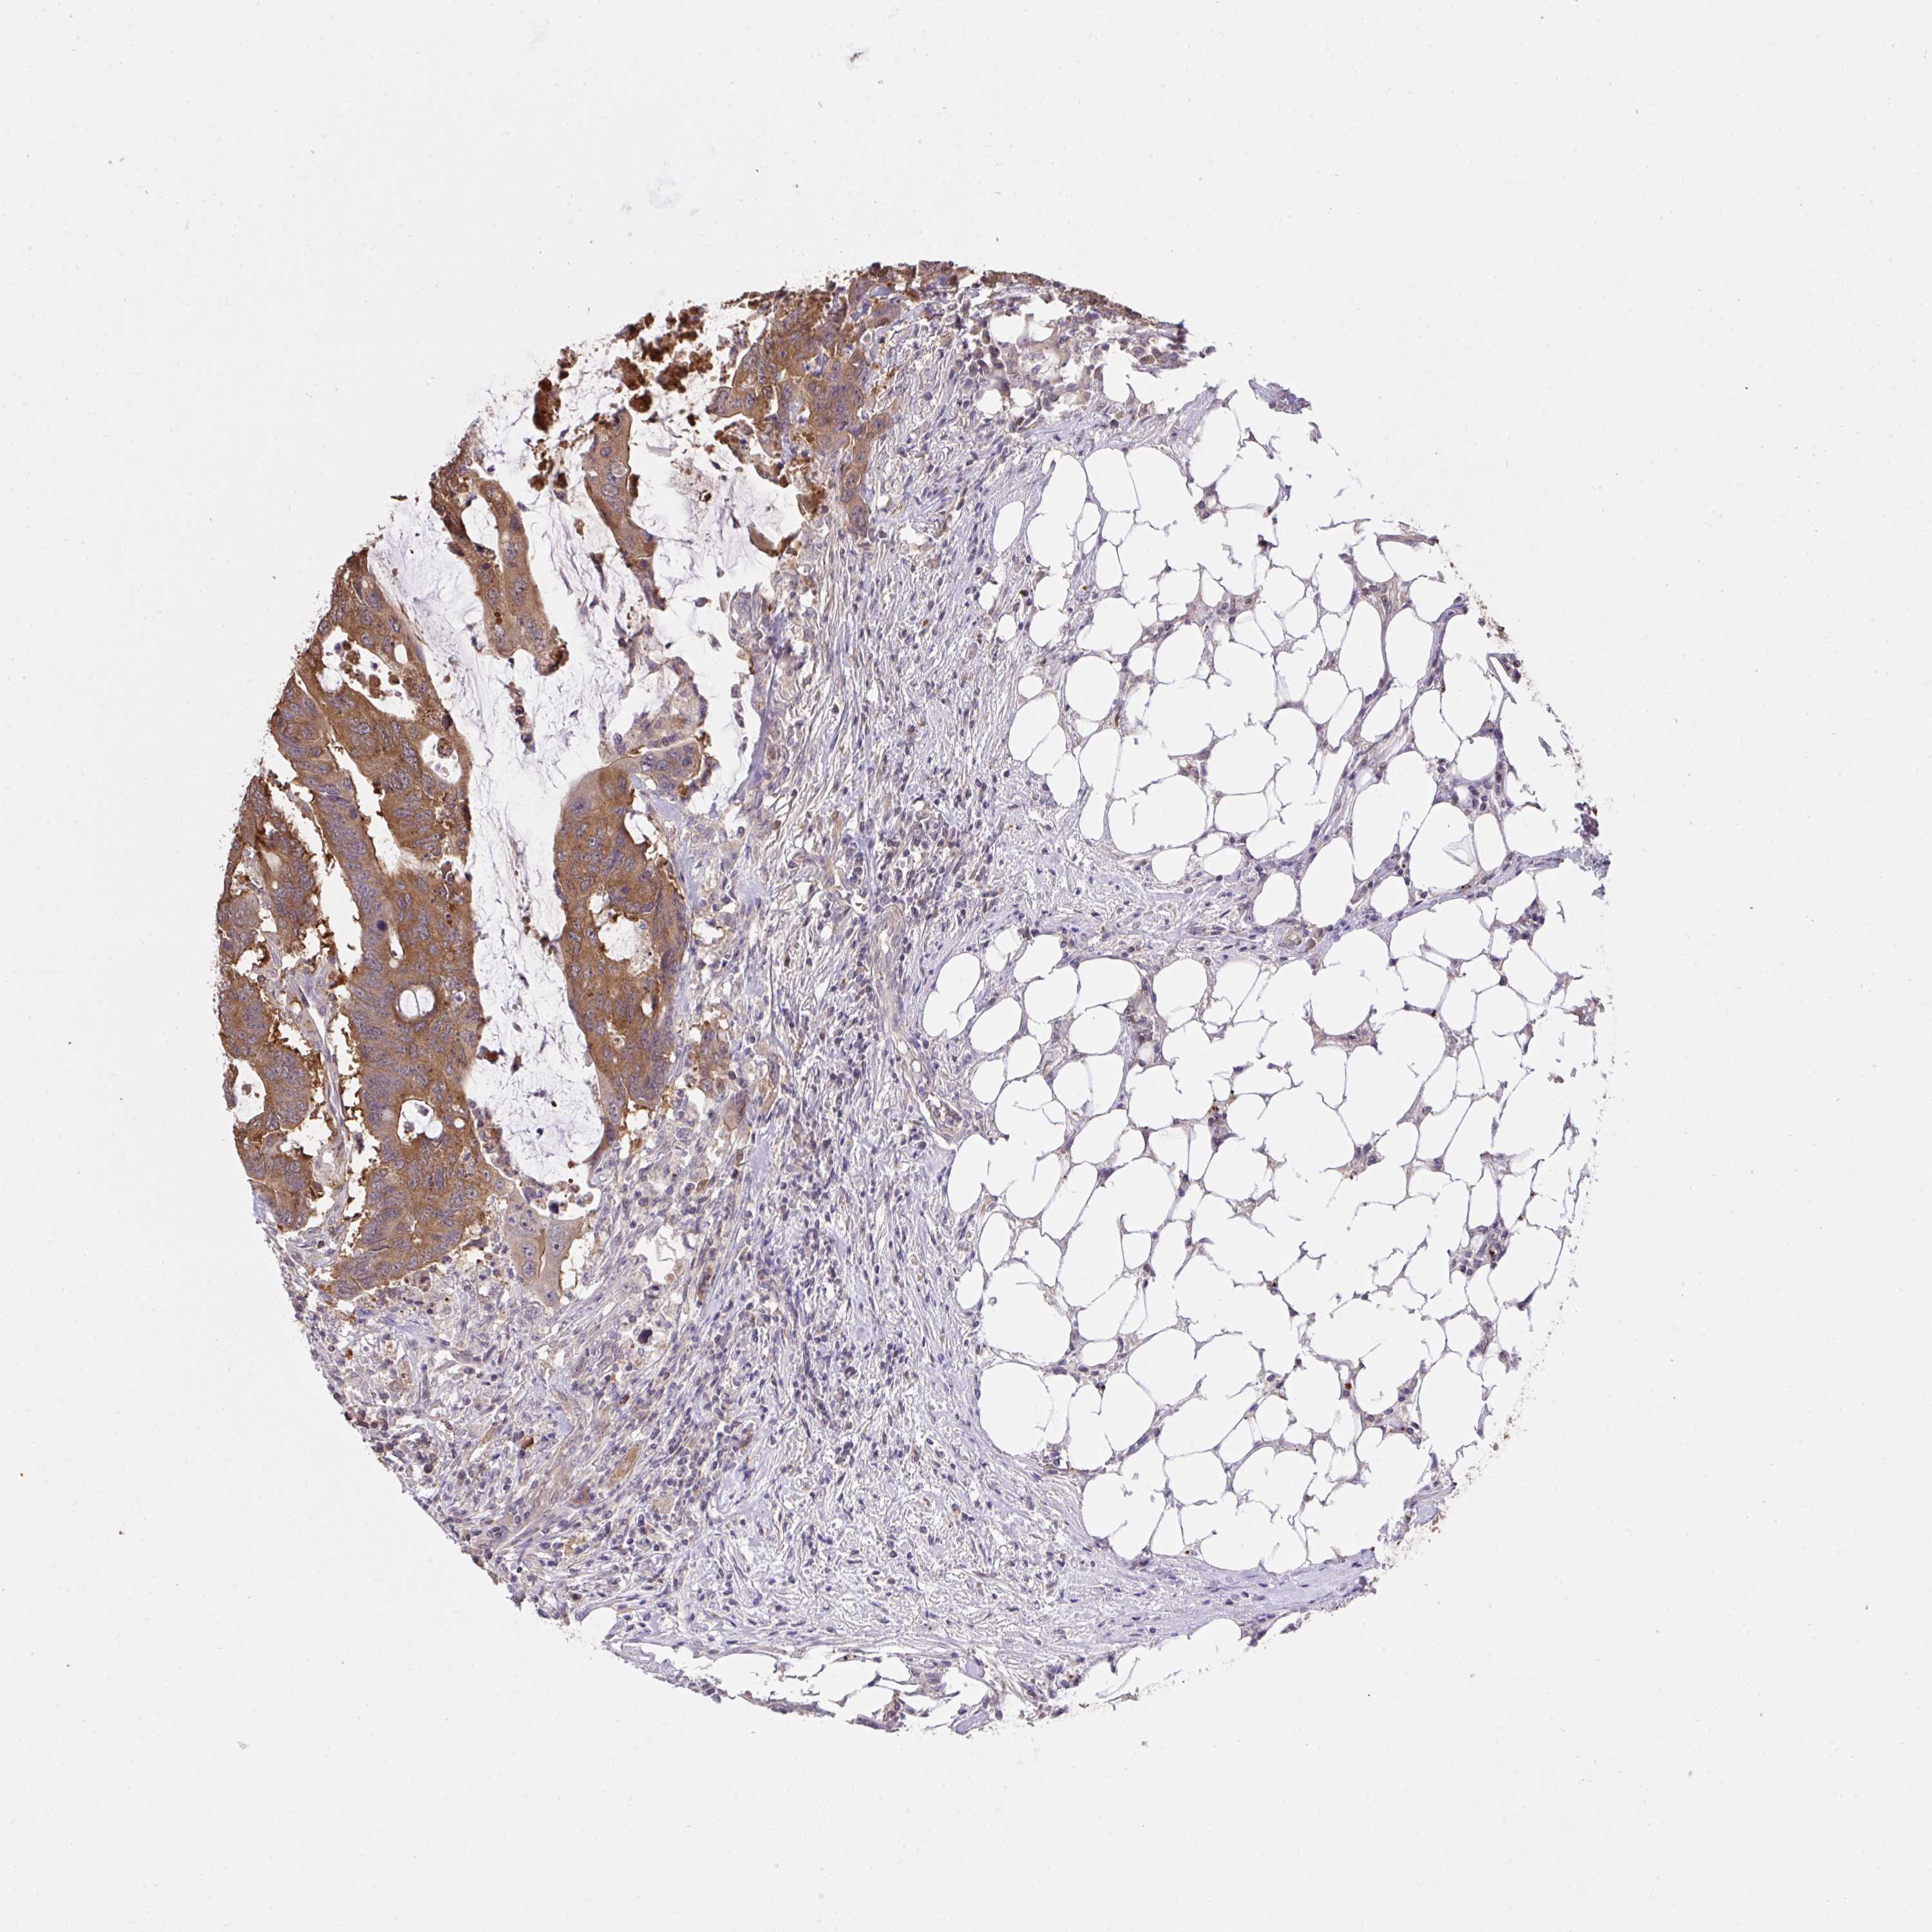

ANTIBODIES

AND

VALIDATION